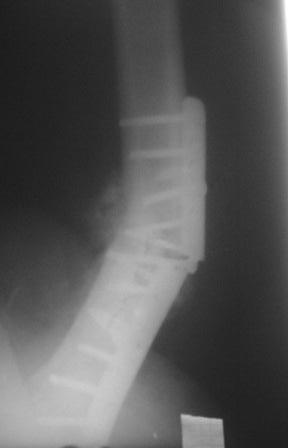

Обратился больной 54г. Травму получил в ноябре 2007г. Оперирован в Алмате (Казахстан). Через 2 мес. гипс снят, потом еще гипс на 2 месяц, с тех пор ходит двумя костылями, последние время беспокоит усиливающаяся боль и деформация.

Локально: укорочение ноги на 3,5см, умеренная отечность и вальгусная деформация, умеренная болезненность, патологической подвижности почти не определяется, но имеется наружная ротация конечности на 15гр.

Наш план БИОС, но так как при удалении пластини зона ложного сустава открывается, для уверенности производить костную пластику (аутографт или хотя-бы по Хахутову) ??, еще как устранить ротацию?

Сегодня больного оперировал.Удаление пластины минидоступом не получилось , т.к. было еше 4 шурупа введенные под разными углами,

они были замурованы к/тканями. Наложено дистракционное устройство по методу А.Н. Челнокова, ротация и угловая деформация устранены, но оказалось в т/б суставе ограничены приведение и внутренная ротация, поэтому пришлось больного укладывать на бок, и с очень большим трудом произведены рассверливание и антеградное введение